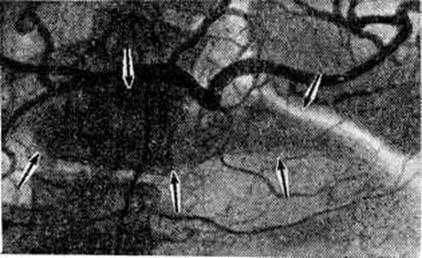

Рентгенодиагностика. При рентгенологическое исследовании желудочно-кишечные тракта обнаруживают в случае увеличения поджелудочной железы смещение желудка кверху и кпереди, расширение дуоденальной петли и уплощение медиального контура нисходящей части двенадцатиперстной кишки (рисунок 1). С помощью релаксационной дуоденографии (смотри полный свод знаний: Дуоденография релаксационная) на этом контуре можно выявить короткие ригидные участки, ряд заострённых углублений в виде игл (спикул), вдавления по краям большого сосочка двенадцатиперстной кишки. На обзорных снимках поджелудочной железы определяют также камни или отложения солей кальция (рисунок 2), а на компьютерных томограммах обнаруживают расширенный и деформированный проток поджелудочной железы. При холеграфии (смотри полный свод знаний) иногда находят сужение дистального отдела общего желчного протока.

При целиакографии можно выделить две формы хронический Панкреатит Для первой формы типичны увеличение поджелудочной железы, её гиперваскуляризация и негомогенное контрастирование в паренхиматозной фазе (рисунок 3). Вторая форма более характерна для Панкреатит с выраженными фиброзными изменениями в поджелудочной железе. Она отличается смещением и сужением сосудов и обеднением сосудистого рисунка. Паренхиматозная фаза отсутствует или ослаблена. При всех формах Тилени Арнешьё(H. Tylen, В. Arnesjo, 1973) наблюдали стенозы крупных артерий вне поджелудочной железы — собственной печёночной, гастродуоденальной, селезёночной. Контуры суженных участков оставались ровными, в то время как при раке поджелудочной железы они имели «изъеденный» характер. Псевдокисты выглядят как округлые аваскулярные образования, смещающие прилежащие артериальные ветви. Во время операции и в послеоперационном периоде (если в протоках поджелудочной железы или полости кисты оставлен катетер для дренажа) для уточнения состояния протоков можно провести панкреатографию (смотри полный свод знаний). Если после операции по поводу кисты образовался наружный или внутренний свищ поджелудочной железы, целесообразно проведение фистулографии (смотри полный свод знаний), которая позволяет охарактеризовать свищевой ход и остаточную полость кисты (рисунок 4).

Рис. 1.

Рентгенограмма желудка и двенадцатиперстной кишки больного хроническим панкреатитом: желудок смещён кверху, двенадцатиперстная кишка развёрнута увеличенной поджелудочной железой.

Рис. 3.